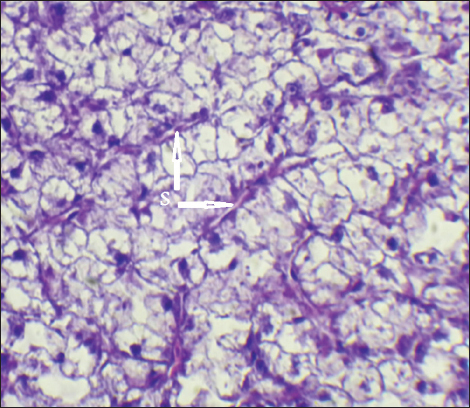

The result of histopathological alteration of the liver revealed degenerative and necrotic changes in liver tissue distinguished by pyknosis with the existence of necrosis in cells (Figs. 14 and 15) also, the result revealed dilation of the sinusoids with cytoplasmic vacuolation (Fig. 16).

Fig. 15. Histopathological sections of liver of C. carpio showing necrosis (N) (H&E X40).

Fig. 16. Histopathological sections of liver of C. carpio showing dilation of the sinusoids (S) with cytoplasmic vacuolation (H&E X40).

It is well known that exposure to heavy metals can cause a variety of histopathological changes (Mustafa et al., 2012). These changes may be related to the harmful effects of heavy metals on hepatocytes, as the liver is involved in the biotransformation and detoxification of various pollutants and toxicants (Arellano et al., 1999). The observed necrosis in certain areas of the liver tissue may have been caused by the fish’s overwork in eliminating the toxins from its body during the detoxification process; this observation is consistent with the findings of Rhaman et al. (2002).